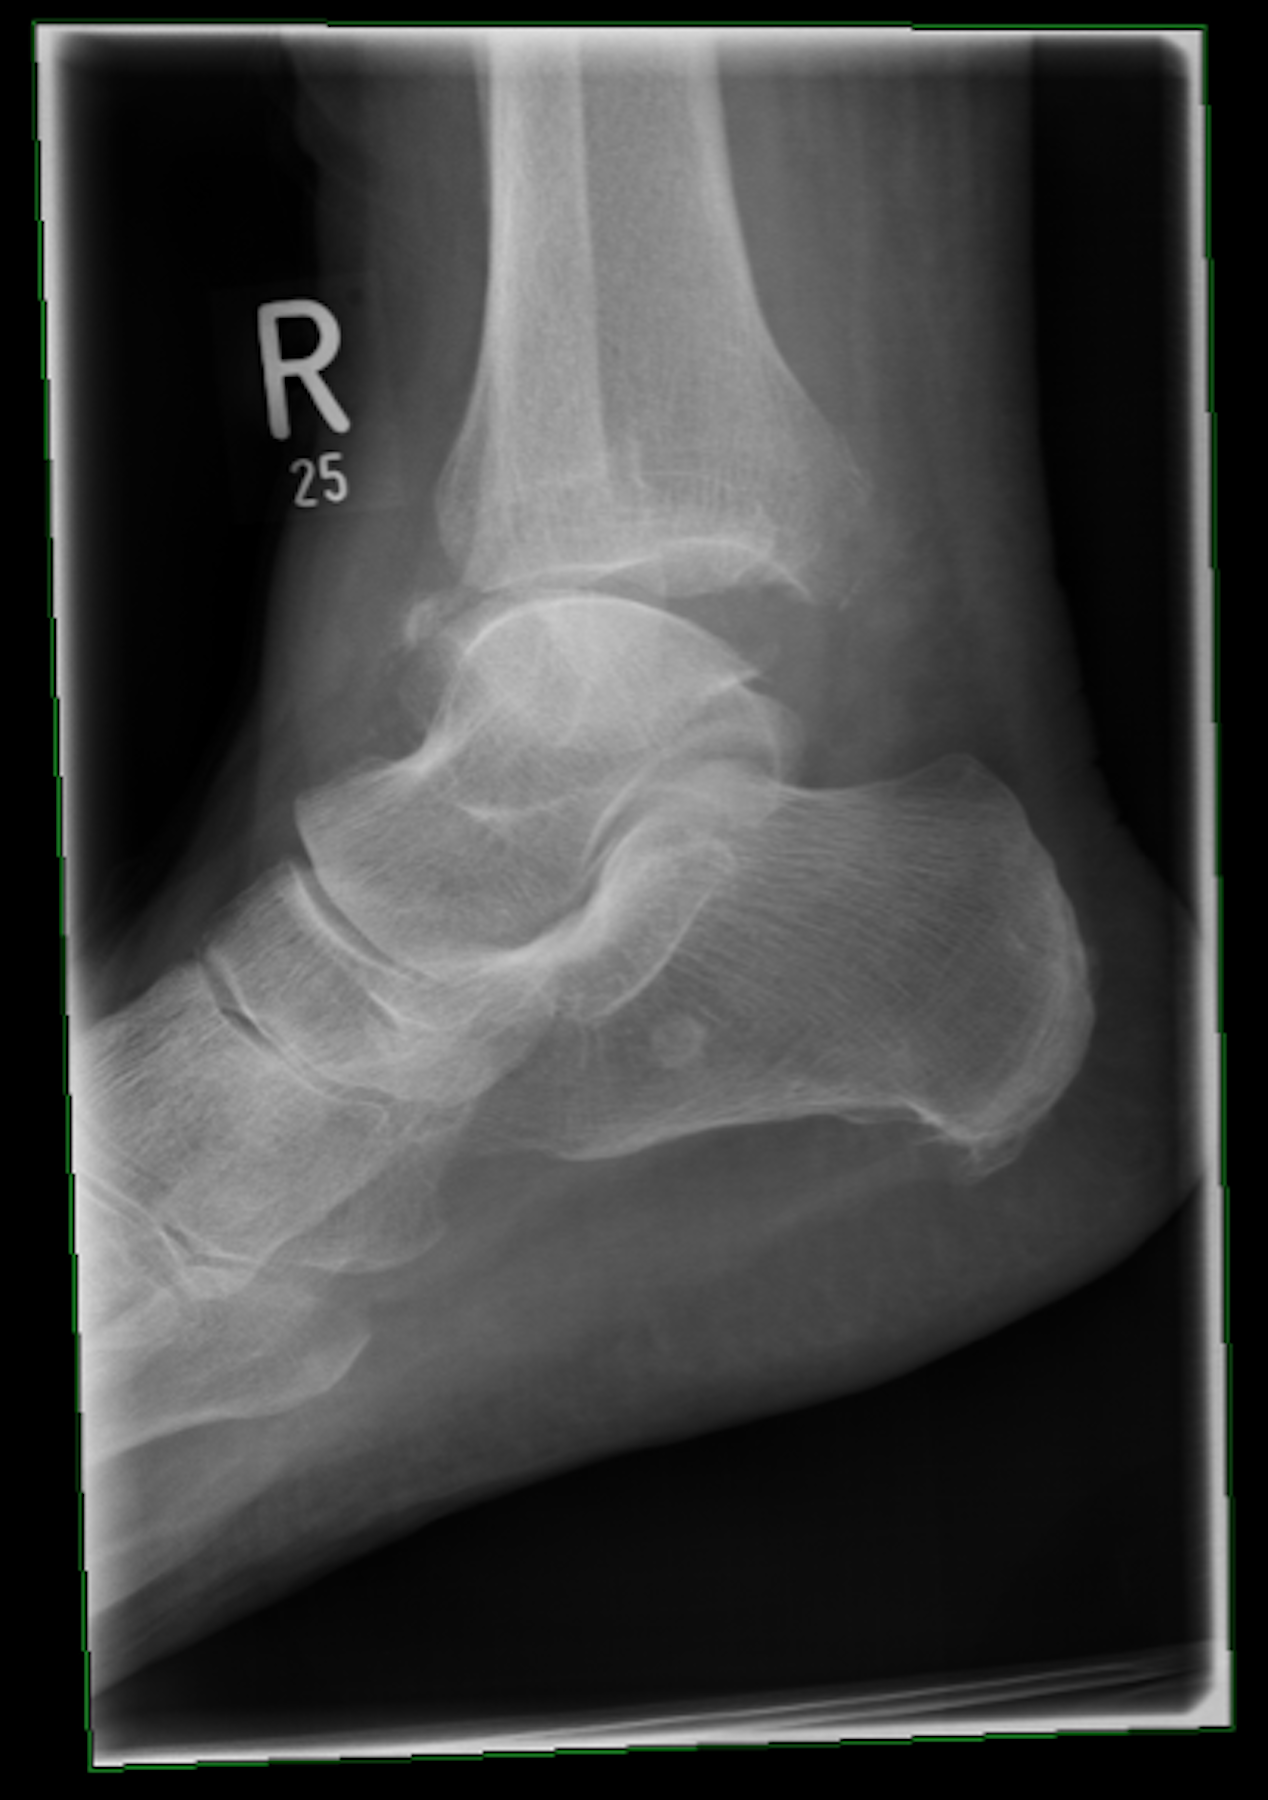

Nach dem ansonsten unauffälligen Bodycheck führen Sie eine Röntgenuntersuchung durch (siehe Abbildungen).